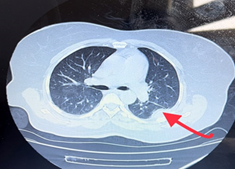

Imaging was ordered and multivisceral metastases were noted: hepatic, pulmonary and vertebral.

Figures 35: Presence of multivisceral metastases with choroidal location as the primary tumor CT-detected.

Figure 3 Vertebral metastasis.

Figure 4 Lung metastasis.

Figure 5 Hepatic metastasis.